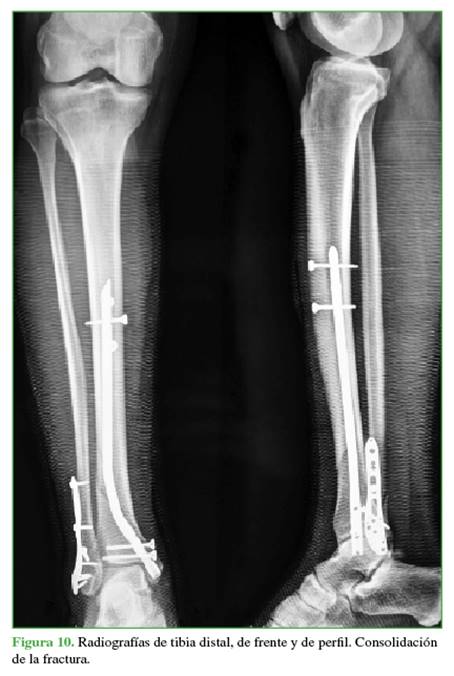

Se introduce el clavo de la longitud planificada bajo control radioscópico y, por último, se acerroja a distal con la guía externa y a proximal, a manos libres (Figuras 8-10).

En 8 casos, la fractura consolidó a los 4 meses de la cirugía y, en los restantes, demoró 5 meses (puntaje RUST 12).

No se observaron deformidades angulares en la tibia distal luego de la consolidación de la fractura. Según la escala de la AOFAS, 12 resultados fueron excelentes y 3, regulares, uno de estos fue el paciente que tenía una fractura expuesta IIIB y necesitó un colgajo libre para la cobertura de partes blandas (Tabla).